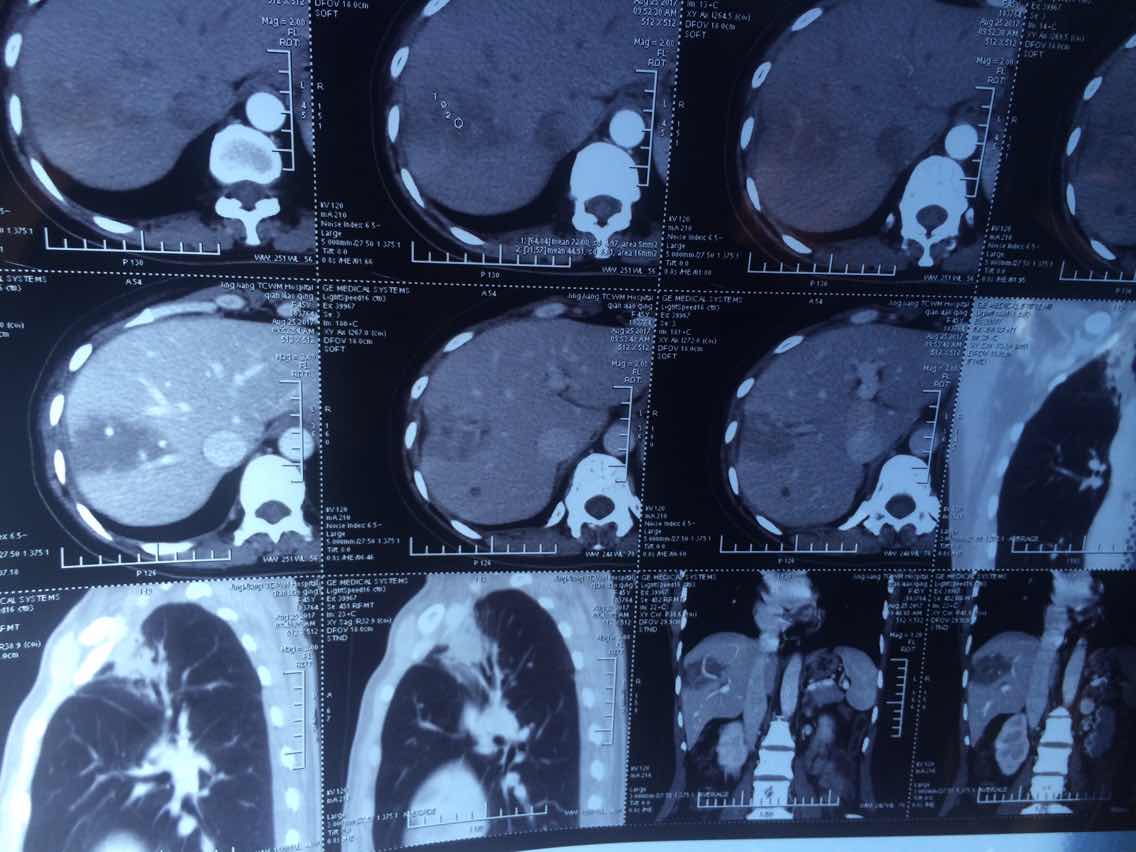

陈医生,这是2016.10.26的ct看看拍的对不

举报

2017-10-31 10:10:21 有用(0)

回复(0)

2

2017-10-31 10:10:42 有用(0)

3

2017-10-31 10:11:05 有用(0)